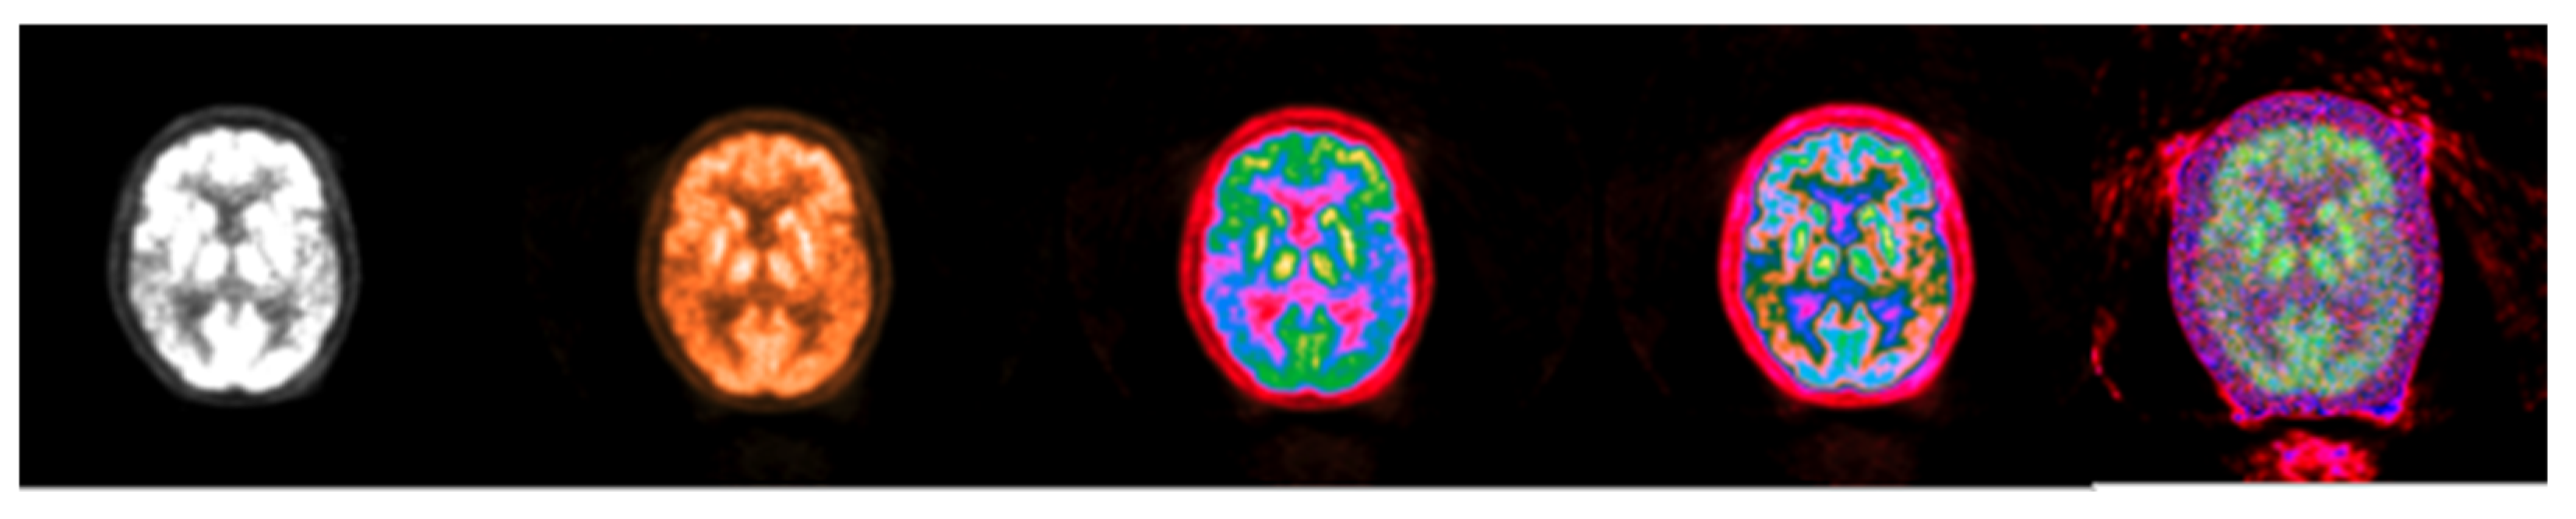

2.2. Method 1: Colormap Information Transform (CIT)

3.1. CIT Application

3.2. Colormap Folding Application